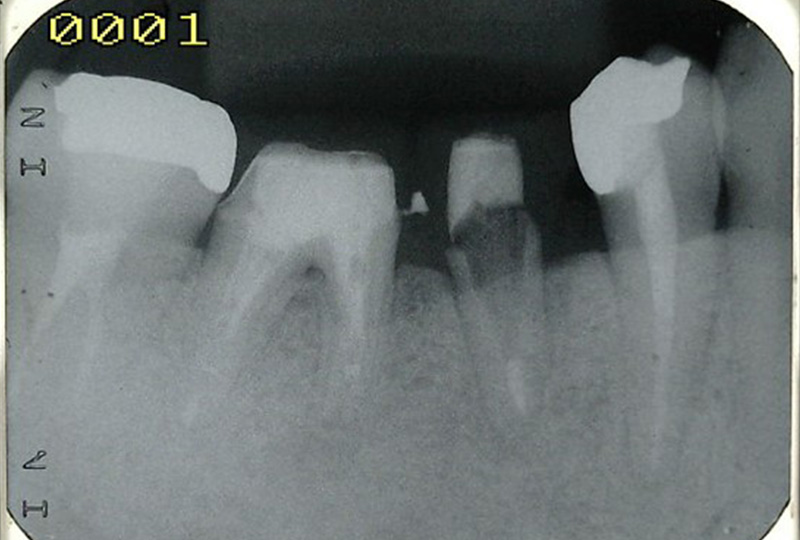

『歯のひび(歯根破折)』など通常であれば抜歯と言われるような歯の保存や歯を失った所に親知らずなどを移動させる『歯の移植』など一般の歯科医院では行わない特殊な治療も行なっております。